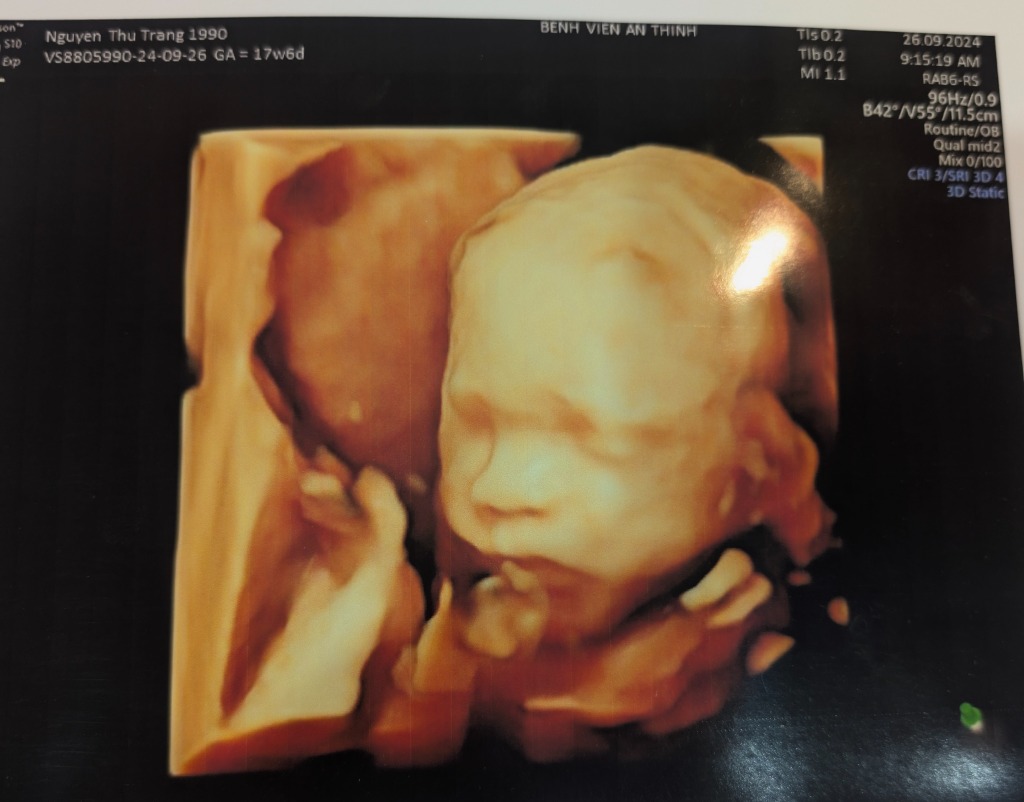

Nguyễn Thu Trang